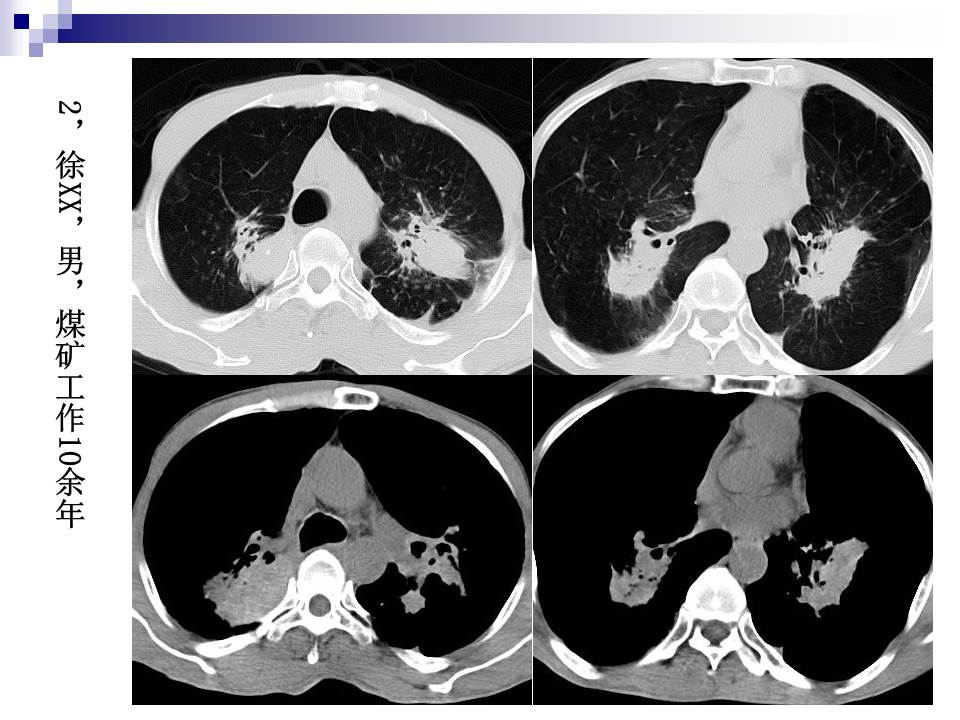

尘肺